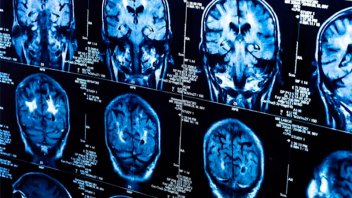

Un doble escáner, uno realizado antes de la pandemia y el otro en los peores meses de la crisis, muestra que los infectados por el coronavirus tienen cambios en el cerebro no vistos en los que han escapado al virus. El estudio muestra que el descenso de materia gris es generalizado, y que las áreas más afectadas son las relacionadas con el olfato. Los autores del trabajo no saben si estos daños son provocados por el virus en sí o son consecuencia de la enfermedad. Tampoco saben si temporales o serán para siempre.

Ahora, un grupo de investigadores de la universidad de Oxford (Reino Unido) ha podido analizar las imágenes del cerebro de casi 800 británicos. El estudio es longitudinal, es decir con datos del mismo grupo de personas en distintos momentos. Eso otorga un extra de robustez a sus resultados. La mitad de los participantes tuvieron Covid entre una resonancia y otra, tomadas con más de tres años de diferencia, lo que ha permitido comparar los cambios inducidos por el coronavirus en el cerebro y cotejarlos con las imágenes cerebrales de los no afectados.

Los resultados, publicados en la revista Nature, muestran que los infectados tenían una mayor pérdida de materia gris y más alteraciones en los tejidos cerebrales. Las diferencias eran más grandes en las partes del cerebro que intervienen en el sentido del olfato, como la corteza orbitofrontal o el giro parahipocampal. Todos estos cambios eran más acusados cuanto más edad tenían los participantes.

Declive en habilidades

La investigadora del Departamento Nuffield de Neurociencia Clínica de Oxford y principal autora del estudio, la profesora Gwenaëlle Douaud, destaca que también han visto “diferencias en regiones no relacionadas con el sentido del olfato, como el polo temporal, el giro supramarginal o el cerebelo”. En cuanto al volumen global cerebral, “hubo una pérdida adicional de un 0,3% entre los participantes infectados”, añade. Esa es la media, pero hay casos de una reducción del total del cerebro del 2%, porcentaje aún mayor en las regiones olfatorias. De nuevo, el deterioro era comparativamente, superior cuanto más edad tenía el sujeto.